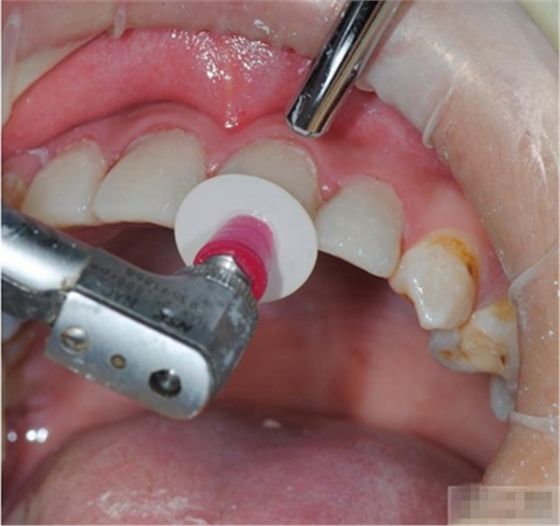

釉質(zhì)邊緣要用橡皮輪拋光

拋光可以去除懸釉。這樣經(jīng)過車針打磨過的釉質(zhì)表面會(huì)更加均一,形成良好的邊緣封閉。